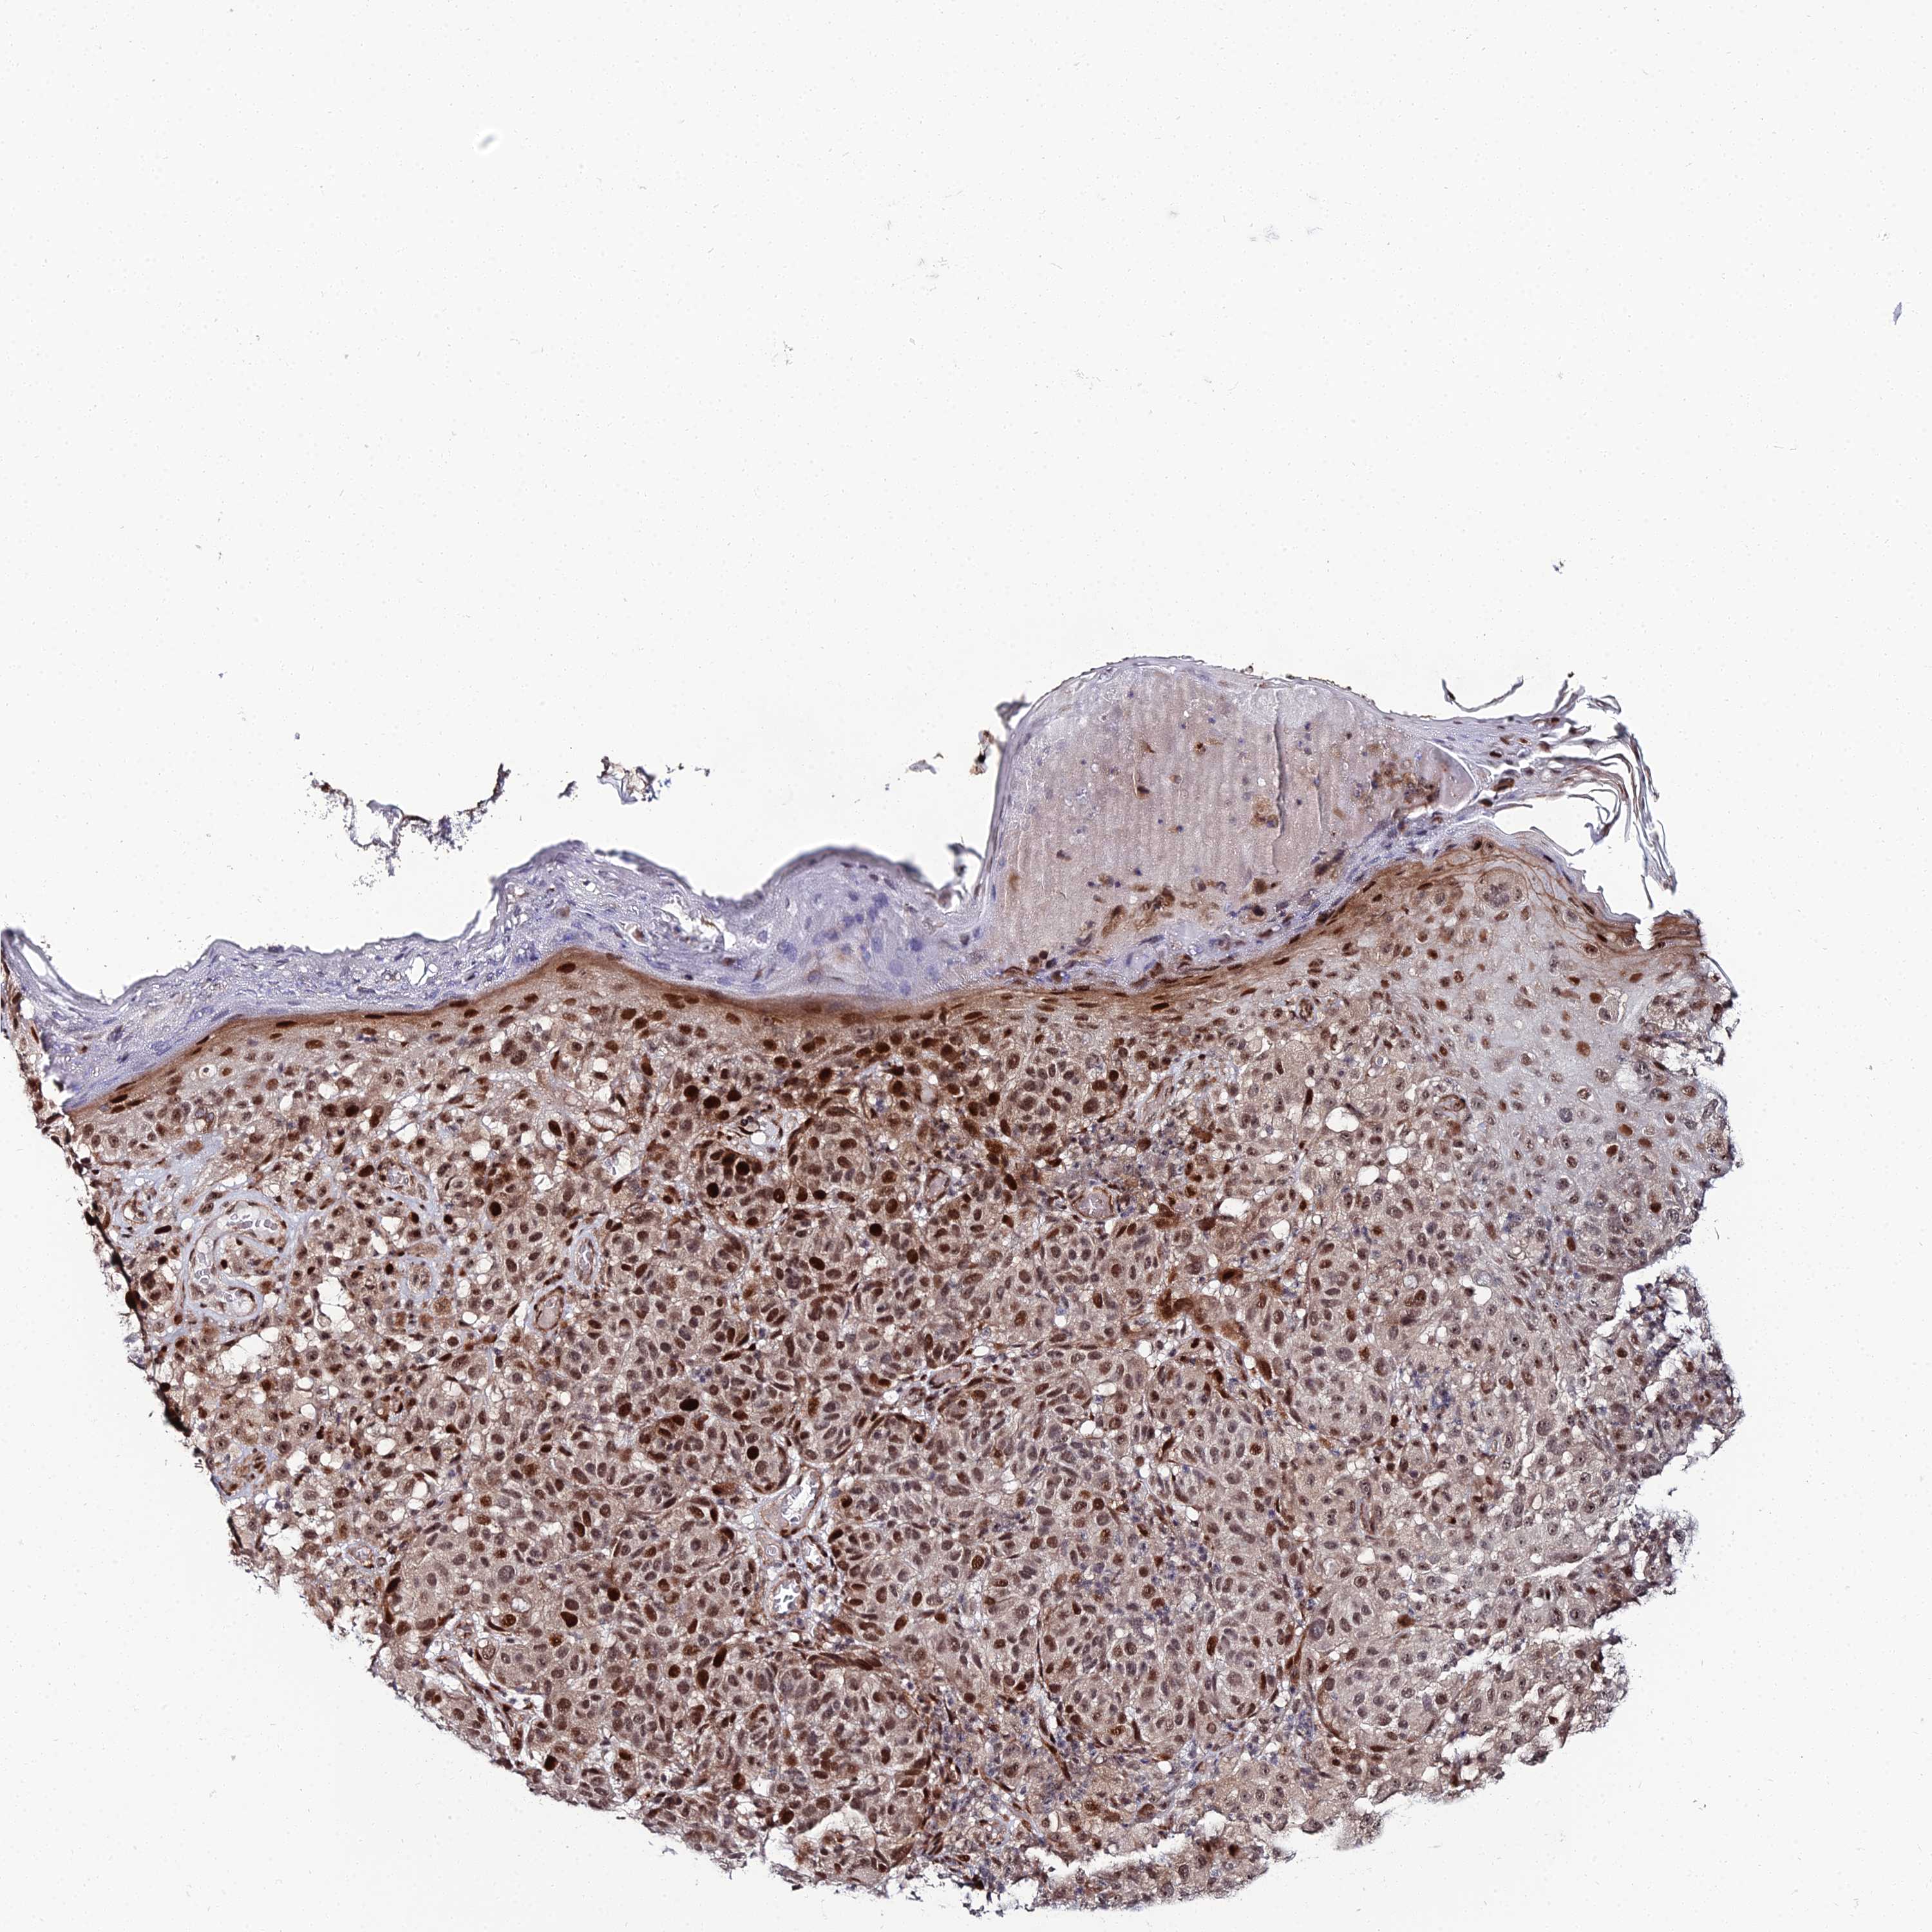

MELANOMA - Protein expressioni

A mouse-over function shows sample information and annotation data. Click on an image to view it in a full screen mode. Samples can be filtered based on level of antibody staining by selecting one or several of the following categories: high, medium, low and not detected. The assay and annotation is described here.

Note that samples used for immunohistochemistry by the Human Protein Atlas do not correspond to samples in the TCGA dataset.

Antibody stainingi

Antibody staining in the annotated cell types in the current human tissue is reported as not detected, low, medium, or high, based on conventional immunohistochemistry profiling in selected tissues. This score is based on the combination of the staining intensity and fraction of stained cells.

Each image is clickable and will lead to virtual microscopy that enables deeper exploration of all samples and also displays staining intensity scores, fraction scores and subcellular localization as well as patient and tissue information for each sample.

Antibody HPA043048

Staining

High

Medium

Low

Not detected

Intensity

Strong

Moderate

Weak

Negative

Quantity

>75%

75%-25%

<25%

None

Location

Nuclear

Cytoplasmic/membranous

Cytoplasmic/membranous,nuclear

Malignant melanoma, NOS

Malignant melanoma, Metastatic site